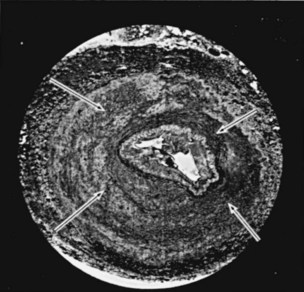

Perimedial fibroplasia occurs predominantly in young women between the ages of 15 and 30 years and has therefore been referred to, rather crudely, as girlie disease. It constitutes about 10% to 15% of the total number of fibrous lesions and occurs only in the renal artery. This is a tightly stenotic lesion that, pathologically, consists of a collar of dense collagen enveloping the renal artery for variable lengths and thicknesses. The collagen is deposited in the outer border of the media, usually replaces a considerable portion of the media, and may replace it completely in some areas (Fig. 39–5). Islands of smooth muscle are occasionally seen trapped within the collagenous ring. Special stains show that the lesion is confined within the external elastic lamina and contained in all cases by intact adventitial connective tissue. The arterial lumen may be further compromised by a process of secondary intimal fibroplasia. It has been suggested that this secondary thickening of the intima is related to slowing of blood flow through a narrowed arterial segment, with resultant platelet and fibrin deposition and subsequent fibrous organization.

Figure 39–5 Cross section of the main renal artery in a girl with perimedial fibroplasia demonstrates a dense collagenous collar (arrows) involving the outer media of the vessel, which causes a severe progressive stenosis.

(From Novick AC. Renal vascular hypertension in children. In: Kelalis PP, King LR, Belman AB, editors. Clinical pediatric urology. Philadelphia: WB Saunders; 1984.)